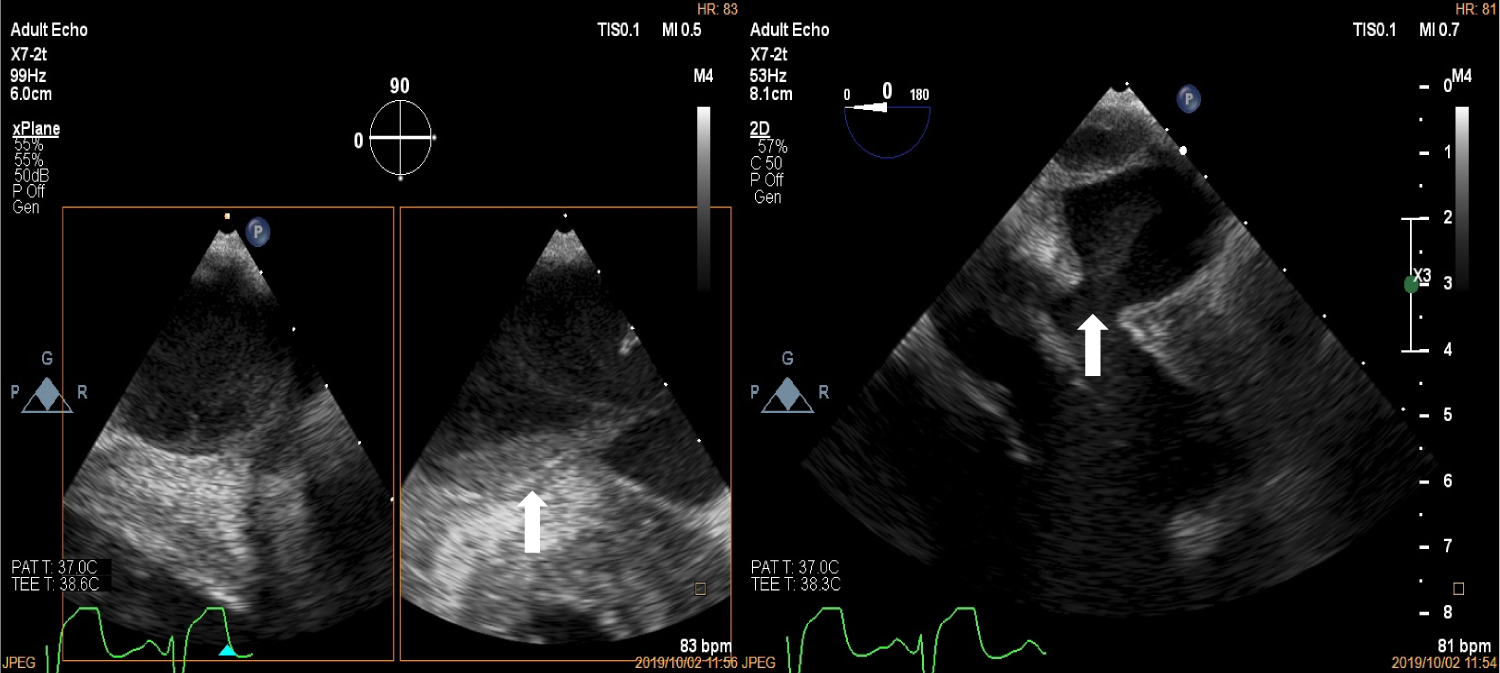

Upon arrival to the cardiology clinic, the patient was noted to be hemodynamically stable with a blood pressure of 126/83 mmHg and heart rate of 88 beats/min. He was not in heart failure. He had a displaced, volume overloaded apex beat and a grade 5/6 pan-systolic mitral regurgitation murmur. Twelve lead electrocardiograms showed sinus rhythm with wide P wave suggestive of left atrial enlargement and early repolarisation. His blood parameters revealed improved Haemoglobin at 11.1 g/dl, CRP of 37 mg/l and a normal urea and electrolytes. He underwent trans-thoracic echocardiography (TTE), which revealed a left ventricular end-diastolic diameter of 62 mm and left ventricular end- systolic diameter of 34.7 mm with an EF of 65%. Right ventricular systolic function was preserved with a trans-annular planar systolic excursion of 2.6 cm and RV S' velocity of 15.5 cm/s. There was severe eccentric mitral regurgitation and severe tricuspid regurgitation with an estimated pulmonary artery systolic pressure of 82 mmHg. No masses or vegetation's were noted. Two discrete aneurysms were noted, one just below the mitral annulus inferior to the posterior mitral leaflet (PML) and the second at the apex of the left ventricle (Figure 1). The patient subsequently underwent two dimensional and three- dimensional transoesophageal echocardiogram (TEE) which confirmed the presence of sub-mitral aneurysm and apical aneurysm. There was spontaneous echo contrast and thrombus in the sub-mitral aneurysm (Figure 2). The PML was perforated revealing two mitral regurgitation jets, one through the perforation and the second was central in origin (Figure 3 and Figure 4). There was also suspicion of oscillating mass on the PML (Figure 3). His blood cultures remained negative. The gene expert for Tuberculosis was negative. He tested negative for syphilis, Human immunodeficiency virus, connective tissue disease and sarcoidosis using the Treponema Haemagglutination test, HIV serology, antinuclear antibody test and serum angiotensin converting enzyme assays, respectively. The patient underwent Multi-detector Computed Tomography (MDCT) to define in detail the anatomical course of the aneurysms and also to exclude coronary artery disease. Multiple left ventricular aneurysms were noted in the posterior wall and the apex (Figure 5 and Figure 6). Aneurysm in the mid-postero-lateral wall measured 38.9 mm × 16.6 mm, sub-mitral aneurysm with thrombus in situ, measured 57.5 mm × 37.8 mm and it dipped inferior to the left atrium (Figure 6). The apical aneurysm in the inferior aspect was calcified at the antero-lateral margin and measured 54.4 mm × 12.7 mm, and in the septal aspect measured 26.9 mm × 14.7 mm. A discrete perforation was noted in the PML measuring 11.1 mm in diameter (Figure 5). There was no significant mediastinal lymphadenopathy.

Figure 1: Two dimensional Transthoracic echocardiogram depicting left ventricular aneurysm at the base in the long axis and short axis views (top left and bottom left marked with white arrows), the apex in the zoomed in 4 chamber view (top right, white arrow) and three dimensional echocardiogram showing aneurysm at the base (white arrow). View Figure 1